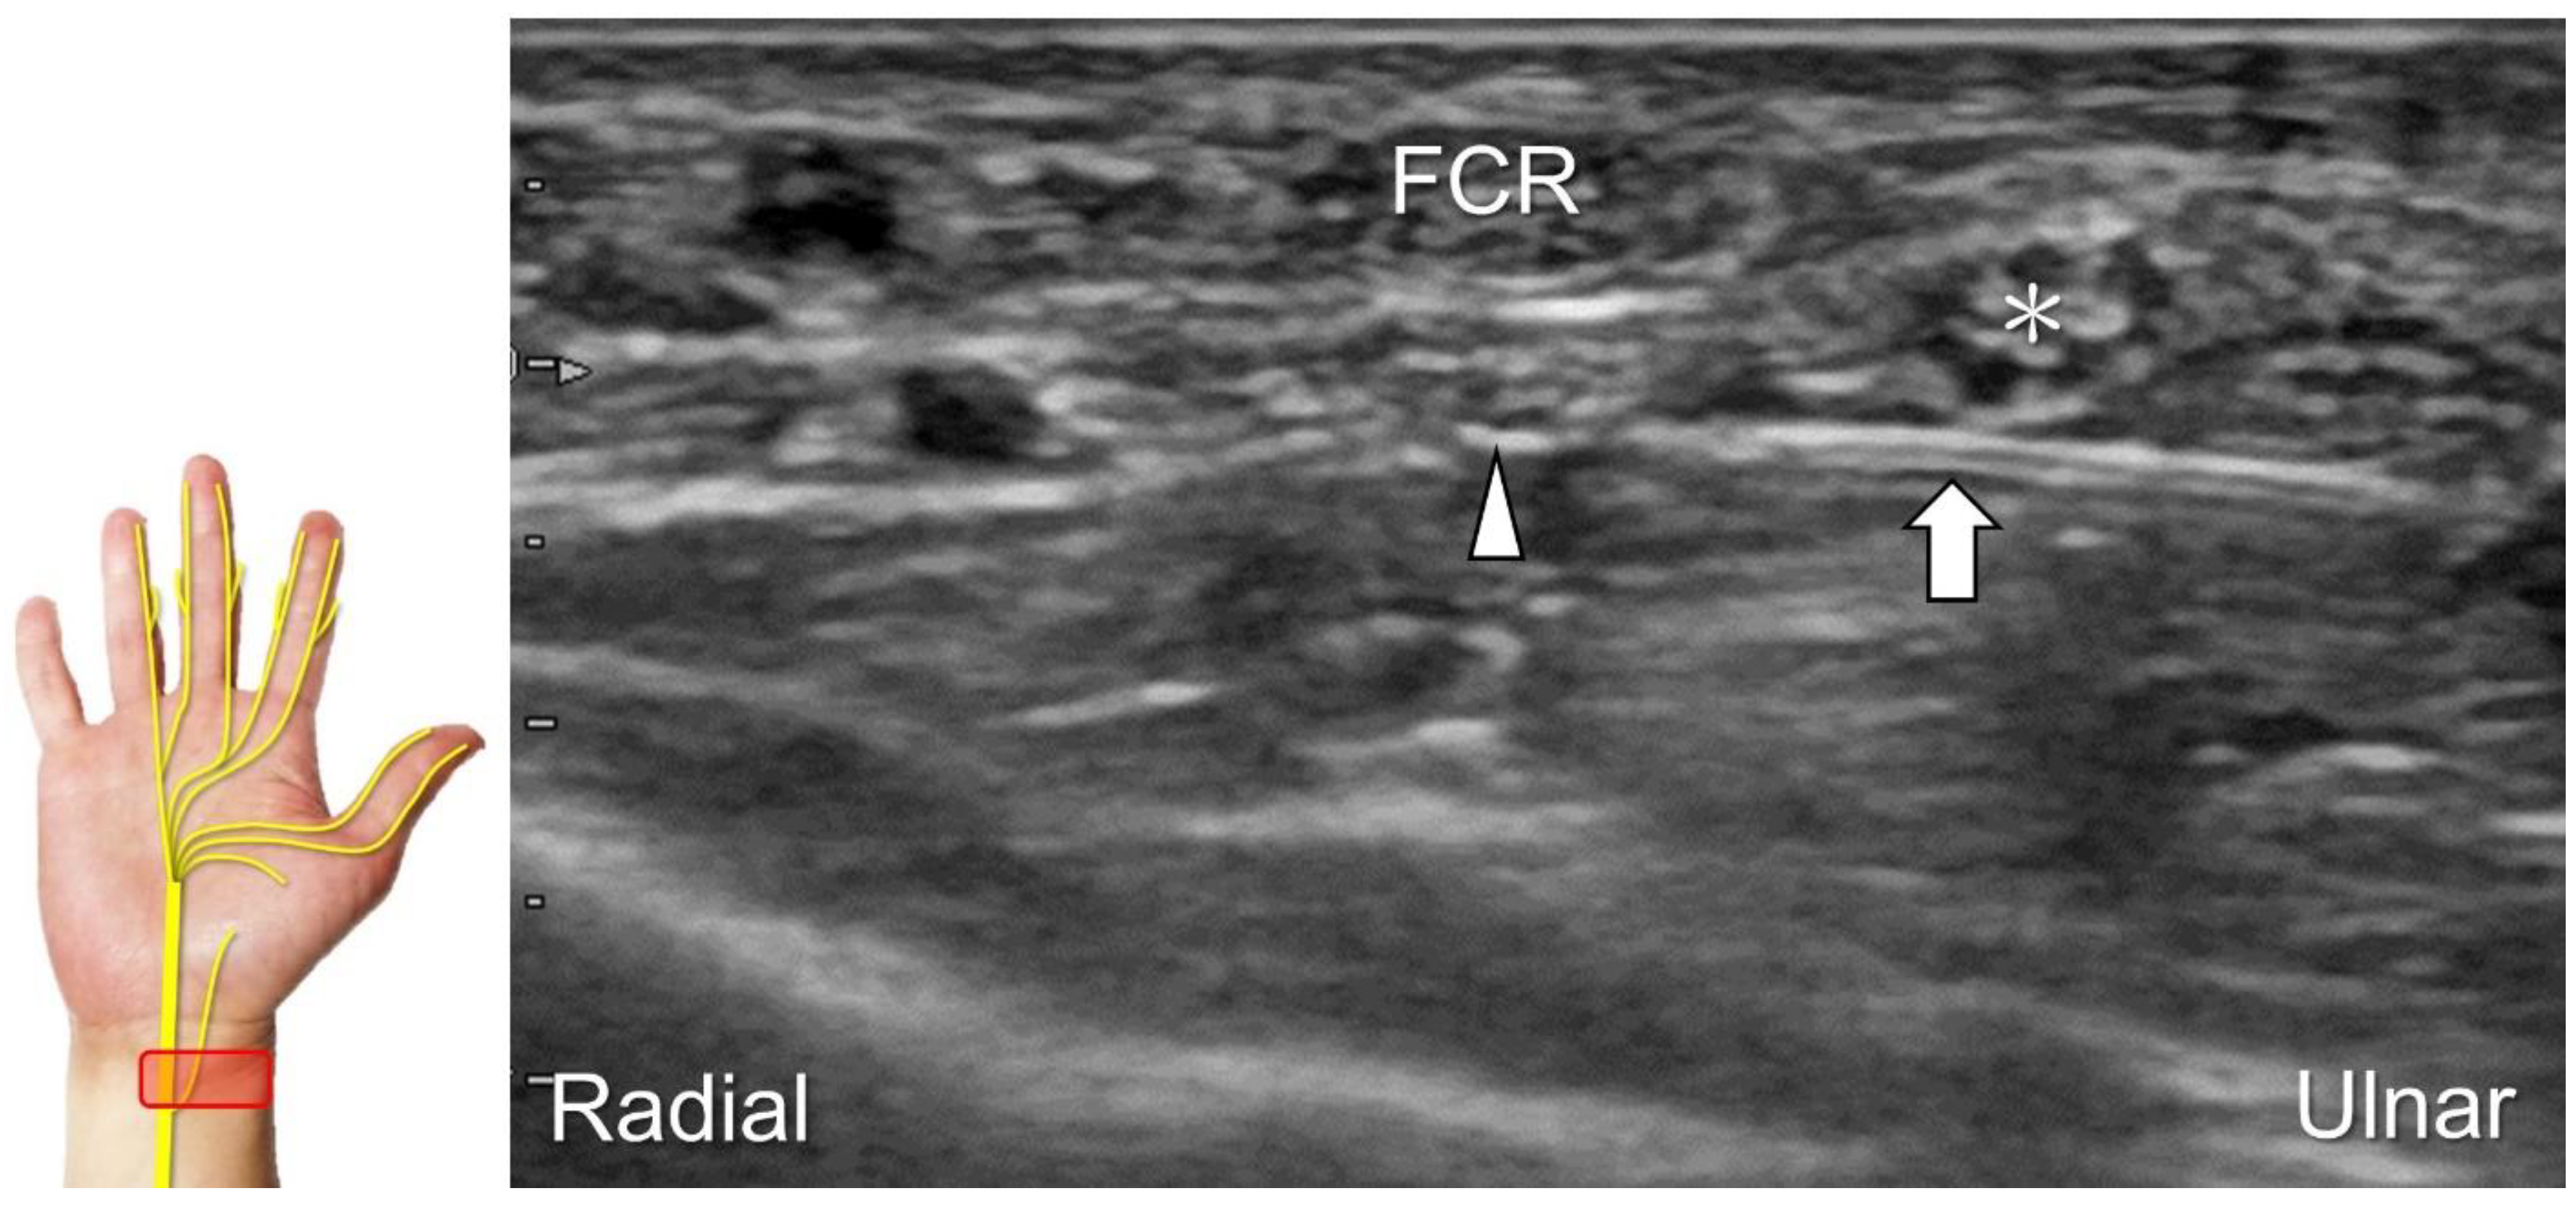

3.1.2. Palmar Cutaneous Branch of the Median Nerve

The palmar cutaneous branch of the median nerve is responsible for sensory innervation to the skin of the thenar and proximal palmar regions. It originates from the radial side of the median nerve in the distal forearm, perforates the antebrachial fascia between the flexor carpi radialis and palmaris longus tendons, and does not enter the carpal tunnel. The nerve then divides into the medial and lateral branches distal to the flexor retinaculum, providing cutaneous sensation to the palm and the ball of the thumb.

Scanning Technique

The transducer is first placed in the axial plane over the distal forearm with the forearm supinated to locate the median nerve between the flexor digitorum superficialis and profundus muscles (Figure 7A). Moving the transducer distally, the palmar cutaneous branch of the median nerve, shown as a single hypoechoic fascicle, emerges from the radial aspect of the median nerve (Figure 7B) [32]. The nerve then penetrates the antebrachial fascia and runs on the ulnar aspect of the flexor carpi radialis tendon (Figure 7C). Eventually, the nerve can be identified superficial to the abductor pollicis brevis muscle (Figure 7D).

Clinical Implication

The palmar cutaneous branch of the median nerve can be injured due to cuts, resulting in neuroma formation (Figure 8A–C) [9]. During an intervention for carpal tunnel syndrome, it is essential to identify the palmar cutaneous branch of the median nerve to prevent accidental injury. Recurrent pain and paresthesia over the palmar region following carpal tunnel release can also be subsequent to entrapment by post-operative scar tissues. For hydrodissection of this nerve, the preferred approach is an in-plane approach targeting its short axis from the ulnar aspect (Figure 9).

Figure 7. Sonographic imaging of the palmar cutaneous branch of the median nerve (A) shows its emerging from the radial aspect of the median nerve (B), penetrating the antebrachial fascia (C), and arriving at the superficial site of the abductor pollicis brevis muscle (D). Asterisk: median nerve; arrowhead: palmar cutaneous branch of the median nerve; dashed line, antebrachial fascia; FCR: flexor carpi radialis tendon; T: trapezium; PL: palmaris longus tendon; AbP: abductor pollicis brevis muscle.

Diagnostics 13 01928 g007

Figure 8. Compared with the normal proximal segment (A), a neuroma originating from the palmar cutaneous branch of the median nerve is seen in short-axis (B) and long-axis (C) imaging. Asterisk: median nerve; white arrowheads: palmar cutaneous branch of the median nerve; black arrowhead: neuroma. FCR: flexor carpi radialis tendon; PL: palmaris longus tendon.

Diagnostics 13 01928 g008

Figure 9. Ultrasound-guided hydrodissection (short-axis view) for the palmar cutaneous branch of the median nerve. Asterisk: median nerve; arrowhead: palmar cutaneous branch of the median nerve; arrow: needle. FCR: flexor carpi radialis tendon.

Diagnostics 13 01928 g009